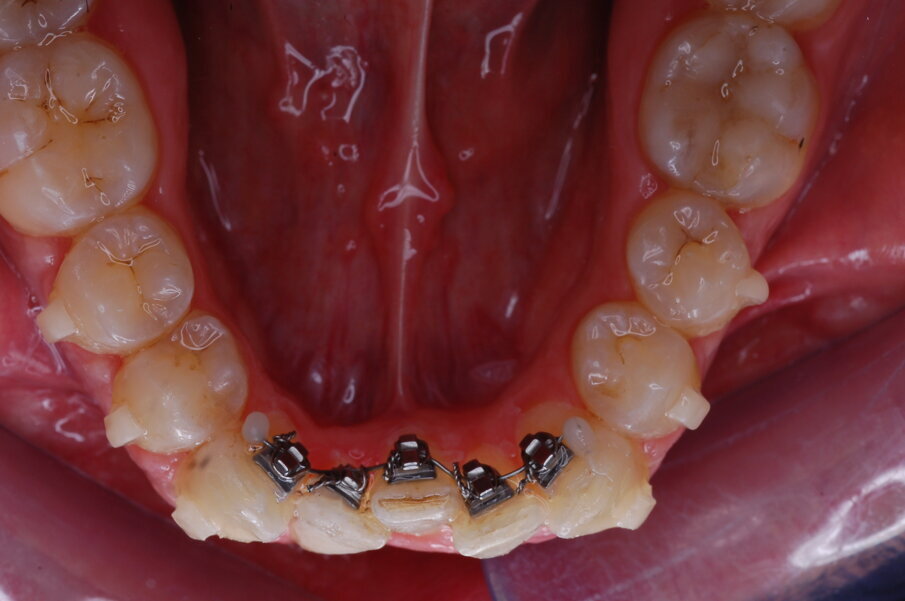

Figg. 25-29_Progressi clinici dopo 12 mesi di trattamento con allineatori.